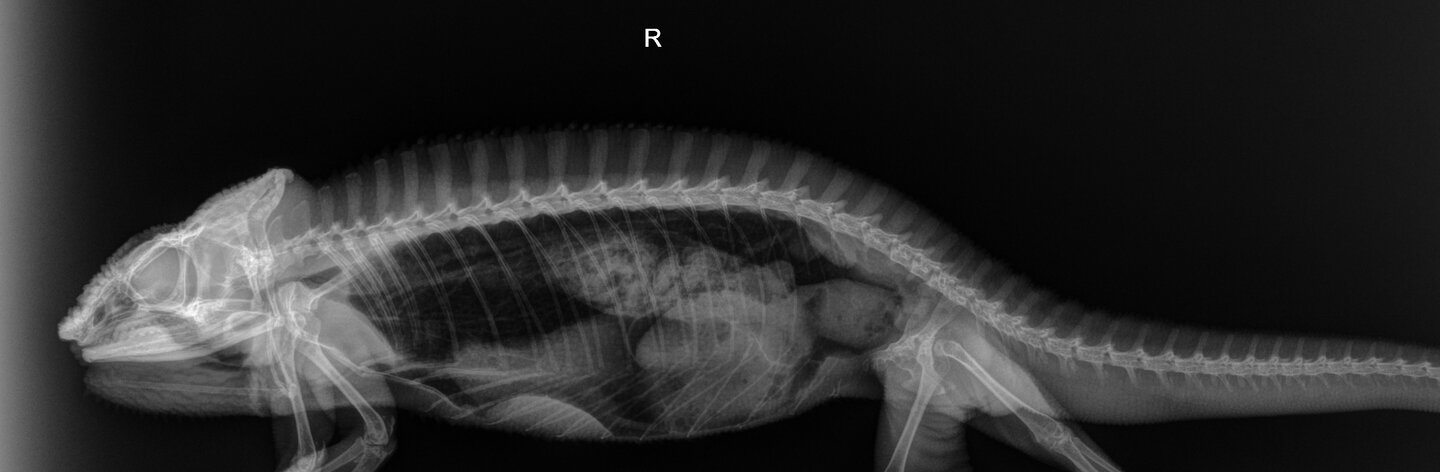

Hi guys! My chameleon Sprinkles has been slightly weaker, falling a lot more often, has poor grip strength. He has been eating and drinking like normal, but his urates are more orange. He is a big boy and is weighing at 280 grams. It progressed over the past few months and he stopped using his tail to move around and stopped curling it at night.

I took him to see Dr. Stein on Saturday at the vet. His X-rays are normal. His blood results showed very elevated Lymphocytes and white blood cells. He is testing for leukemia as well, when he said this I got really freaked out. Do I need to prepare for the worst?